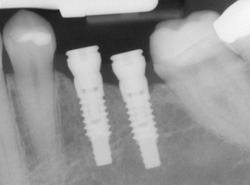

An implant is a synthetic tooth root in the shape of a post that is surgically placed into the jawbone. The “root” is usually made of titanium: the same material used in many replacement hips and knees, and a metal that is well-suited to pairing with human bone. A replacement tooth is then fixed to the post. The tooth can be either permanently attached or removable. Permanent teeth are more stable and feel more like natural teeth.

Single or Multiple Implants

Implants are versatile. If you are only missing one tooth, one implant plus one replacement tooth will do the trick. If you are missing several teeth in a row, a few strategically placed implants can support a permanent bridge (a set of replacement teeth). Similarly, if you have lost all of your teeth, a full bridge or full denture can be permanently fixed in your mouth with a strategic number of implants.